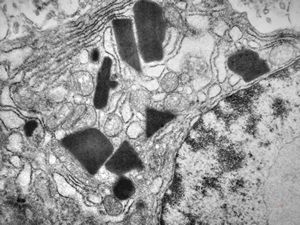

M,59y. | nasopharynx - crystalline inclusions - plasmocytoma